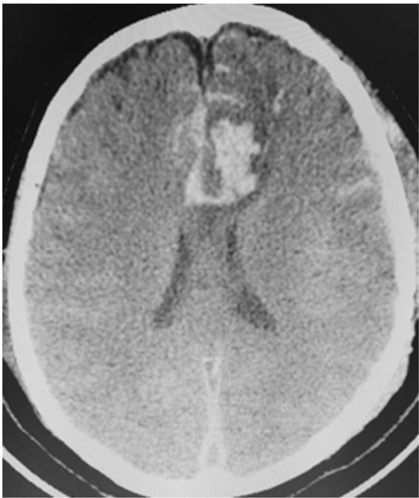

Uma paciente de 66 anos de idade, tabagista, hipertensa com tratamento irregular. Apresentou cefaleia súbita de severa intensidade associada a náuseas. Ao exame físico, observaramse AC = RR2T com BNF, FC = 100 bpm, AP = MVF sem RA, FR = 15 irpm, PA = 182 mmHg x 100 mmHg, SatO2 em ar ambiente = 97%, Glasgow 15, pupilas isofotorreagentes, sem deficits focais. TC crânio e arteriografia a seguir.

Fonte: Acervo pessoal.